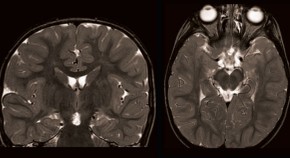

• Neurological morbidity is common in children who have undergone convulsive status epilepticus (CSE), so a recent study evaluating the utility of MRI in determining the extent of brain lesions following CSE is welcome. How might imaging results from children with CSE influence diagnostic, prognostic, and therapeutic decisions?

• Rima Nabbout

• Olivier Dulac

News & Views

Nature Reviews Neurology

Volume: 8, P: 243-244